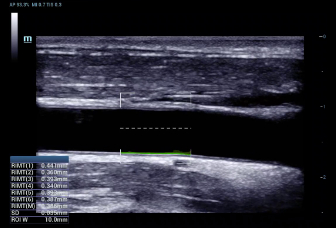

RIMT (RF-Data IMT — измерение толщины комплекса интима-медиа с помощью данных из радиодиапазона)

За счет содержащихся в необработанном акустическом сигнале данных из радиодиапазона (RF-Data), технология RIMT обеспечивает автоматическое измерение толщины КИМ в режиме реального времени с исключительно высокой точностью до 5 мкм, с количественным анализом в пределах 6 сердечных циклов и с меньшей зависимостью от качества изображения – все это значительно повышает точность диагностики.

resona6_gi6

• 09 Auto IMT

Авто IMT (толщина интимы-медии)